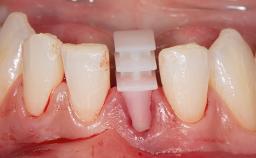

This case from Amélie Mainjot and France Lambert shows how the choice of a screw-retained restoration—which allows adjustment of the profile design over time—was key to managing complications successfully. The authors’ strategic approach avoided a crown remake while also compensating for a soft tissue mismatch. A healthy 20-year-old woman, a non-smoker, presented at the emergency department of the University Hospital of Liège in February 2011 with multiple vertical fractures of tooth 21, incisal fractures of tooth 31, and an enamel and dentin fracture of tooth 32. No tooth luxation was observed. Radiographs confirmed multiple root fractures on tooth 21, including a vertical infrabony fracture, indicating that the tooth was not restorable. A pulpectomy of tooth 21 and an indirect pulp cap on tooth 32 using resin-modified glass-ionomer cement (RMGIC) (Vitrebond; 3M, St. Paul, MN, USA) were performed. RMGC (Fuji IILC; GC, Tokyo, Japan) provisional restorations were placed on the injured teeth. The patient was sent for 3D imaging (multislice CT) the next day to determine the replacement strategy for tooth 21. Because of the vertical fractures, it was important to extract tooth 21 within a few days after the trauma to limit the risk of bacterial infection and consequent tissue loss.